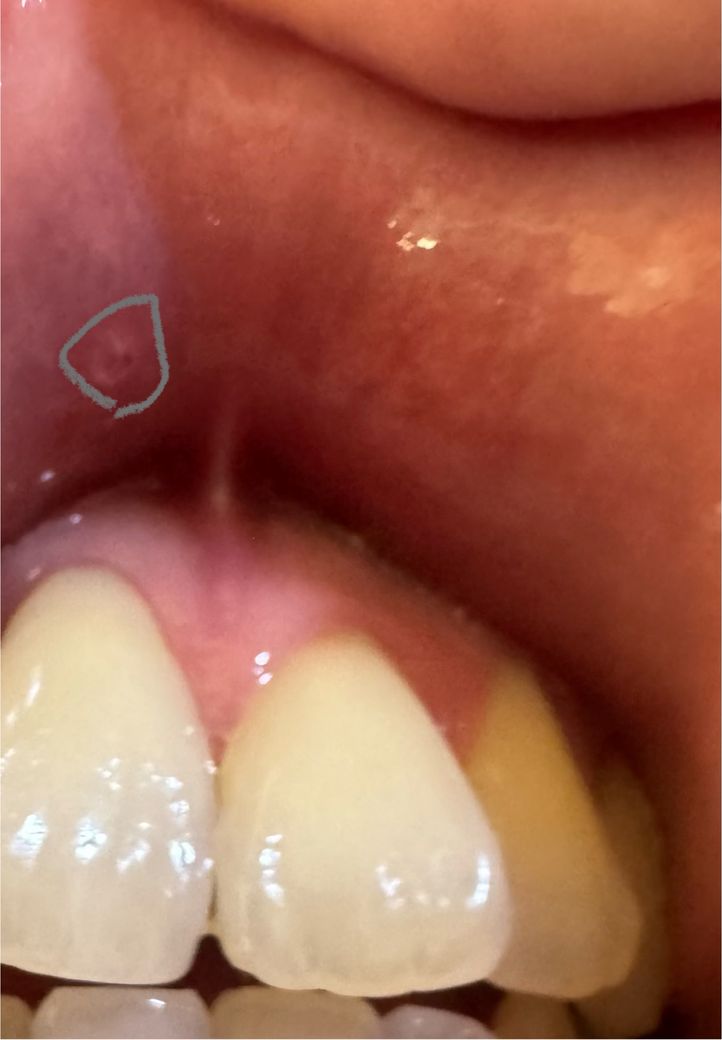

입술안쪽에 하얀수포? 하나가 생겼는데요

아침에 앞니 위쪽 입술 안쪽이 느낌이 이상해서

확인해 봣는데 사진속처럼 하얀투명 물집? 수포?

같은게 하나가 생겼는데요. 지금 감기에 걸려서

일주일째 감기약을 먹고 있는데 따로 수포 때문에

병원안가봐도 될까요? 따로 연고나 관리법좀 알려주세요

현재 집에 에크로바연고랑 오라메디밖에 없는데

처방전없는 연고 추천이랑 관리법좀 알려주세요.

• 1번 째 사진

몸 상태가 좋지 않으면 구내염이 잘 생긴답니다. 증상이 심하지 않다면 그냥 놔두셔도 됩니다. 만약 아프다면 집에 있는 오라..메디 연고를 발라 보셔도 도움이 될 수 있답니다.